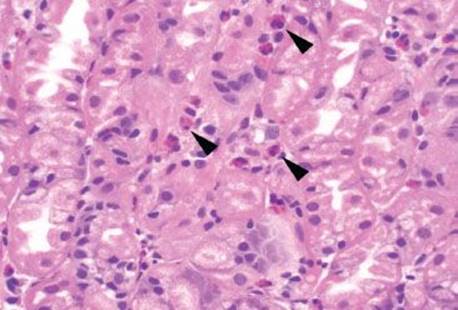

Figure 2.155 Gastric mucosal eosinophilia pattern, eosinophilic esophagitis (EoE). Numerous eosinophils (arrowheads) are percolating between the oxyntic glands of this gastric biopsy. This patient has an established diagnosis of EoE. Gastric mucosal eosinophilia in association with EoE has been reported, but is relatively uncommon. The association between these two entities is unclear.